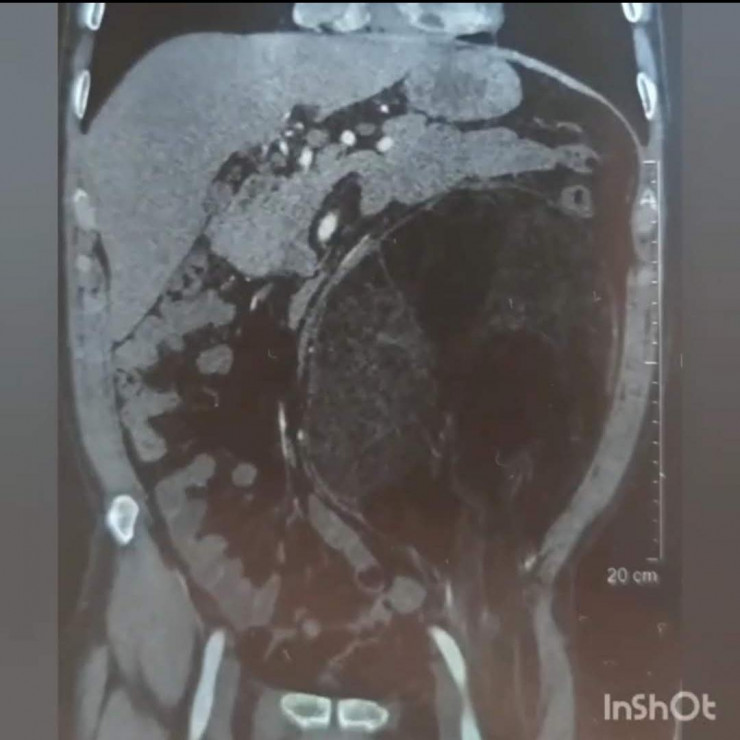

На КТ было обнаружено объемное образование. После тщательных анализов и обследований консилиум решил делать операцию по удалению образования.

Пациенту был выставлен диагноз – образование забрюшинного пространства с переходом в пахово-бедренную область слева.

"Сложность операции заключалась в самом расположении образования. Оно сдвинуло все органы брюшной полости в одну сторону, разместившись на всей левой половине. Границы образования находились очень близко к аорте, образование практически лежало на аорте, прилегая к левой почке и мочеточнику, а внизу образование ушло через паховую область, проходя совсем рядом с бедренной артерией в верхнюю треть бедра. Сложность доступа заключалась в том, что нужно было сделать дополнительный разрез в паховой области. Чтобы извлечь образование, пришлось в три руки очень осторожно отделять образование от органов, к которым оно буквально приросло. Образование удалось извлечь, не нарушив целостности, что очень важно", - объяснил заведующий операционным блоком ГБСНП Нуркен Желдибаев.

На момент операции размер образования был 25-30 сантиметров, а вес образования составил 2,240 килограмма.